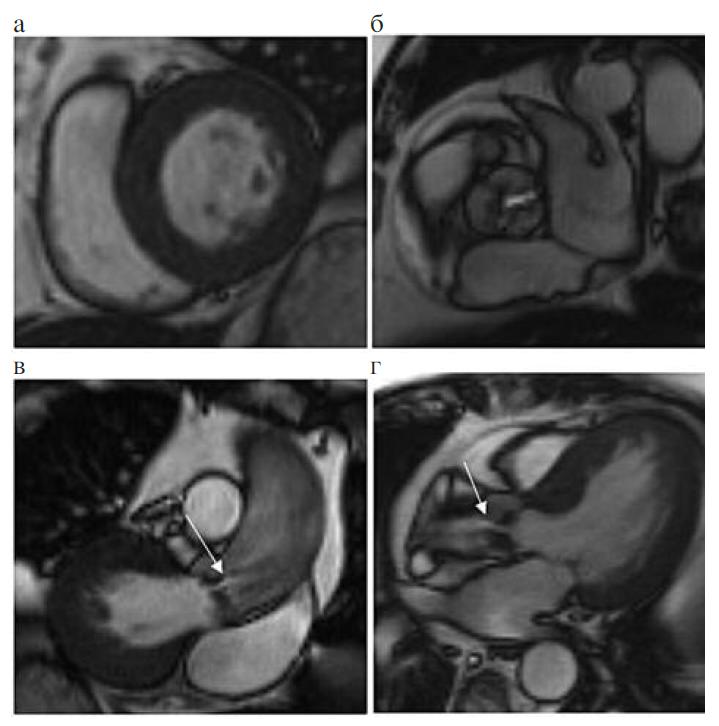

МРТ – метод, дающий как морфологическую, так и функциональную информацию, имеет важное значение для оценки клапанного поражения сердца. МРТ высоковоспроизводимый метод, его точность доказана многими посмертными исследованиями сердца животных и человека [9]. В рамках одного исследования возможно получить изображения высокого качества в любой плоскости, оценить тяжесть поражения клапанов сердца и анатомию связанных с ним крупных сосудов, глобальную и регионарную сократимость. МРТ дает четкую визуализацию субклапанного и надклапанного АС, позволяет оценивать парапротезную аортальную регургитацию (ПАР). Кроме того, МРТ позволяет дать тканевую характеристику миокарда, оценить перфузию и жизнеспособность ткани. Стандартная МРТ сердечно-сосудистой системы проводится на задержке дыхания пациентом. Исследование включает серию ортогональных поперечных срезов, длинную (2- и 4-камерные проекции) и короткую ось ЛЖ (через базальный, средний и апикальный сегменты) в кинорежиме [10]. Для оценки клапанного аппарата, объемов ЛЖ и правого желудочка, систолической и диастолической функций, определения массы миокарда и степени гипертрофии миокарда используют изображения, выполненные через анатомические оси сердца и короткую ось ЛЖ в режиме кино-МРТ со светлой кровью (рис. 1).

Рис. 1. МР-изображения сердца в кинорежиме, дающие анатомическую и функциональную информацию (собственное наблюдение): а – короткая ось ЛЖ, базальный сегмент, диастола (отмечается концентрическая гипертрофия миокарда); б – трехстворчатый аортальный клапан в систолу; в, г – выносящий тракт ЛЖ, систола (стрелки указывают на стеноз аортального клапана).